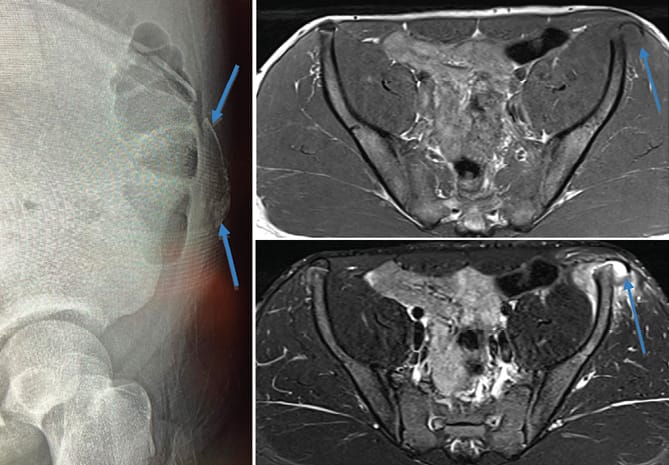

Thérapie manuelle Diagnostic kinésithérapique d'une névralgie clunéale (syndrome des nerfs cluniaux inférieurs) (1ère partie)